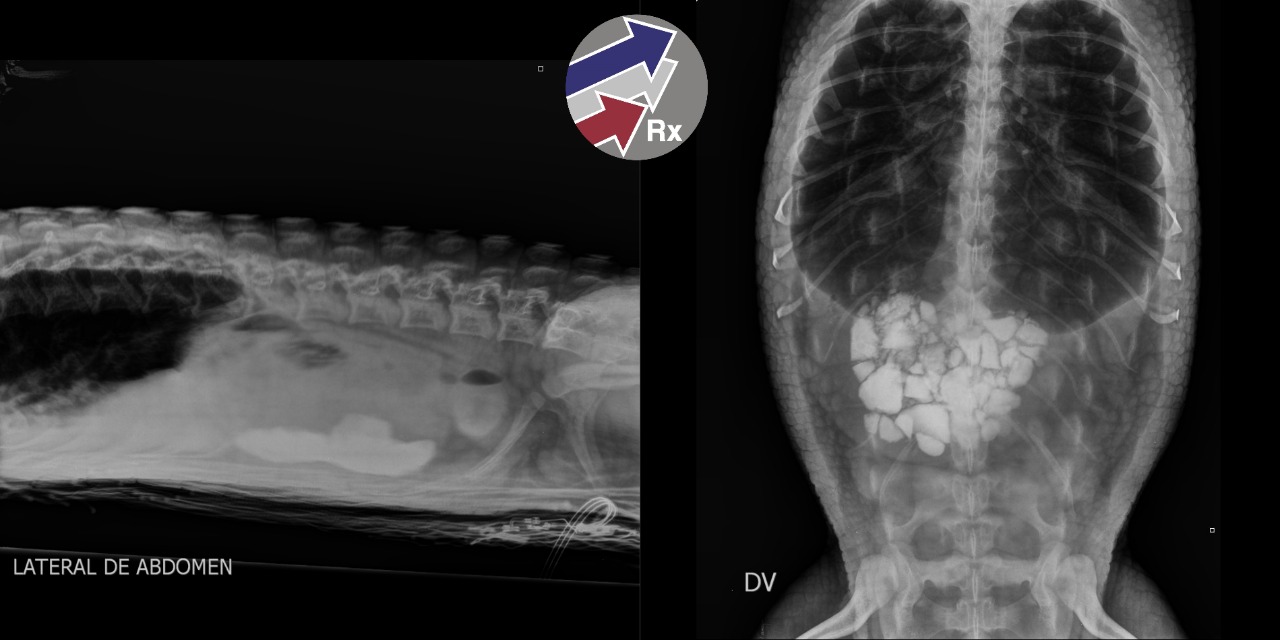

RAYOS X PARA MASCOTAS